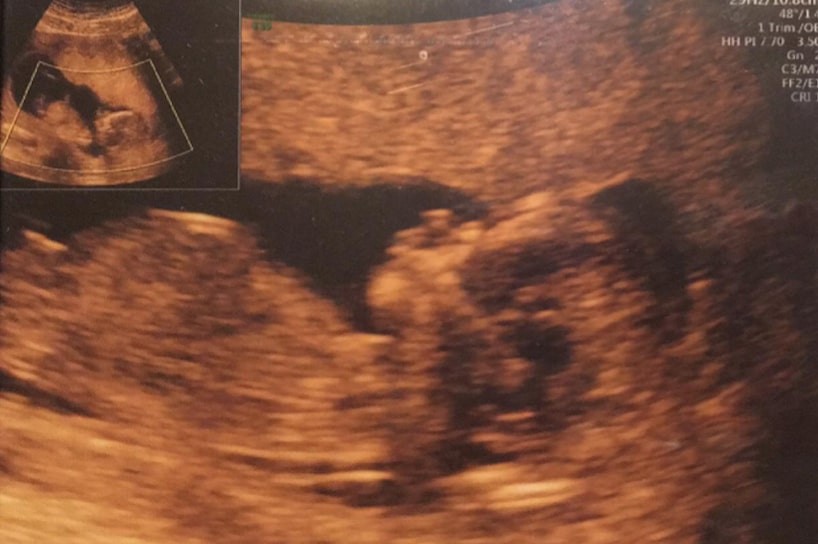

Přiznám se, že ten den stál za prd. Pořád jsem se dívala na jediný UTZ snímek mého chlapečka, mého broučka a nemohla uvěřit, že se mi může brzy zhroutit vysněný svět.